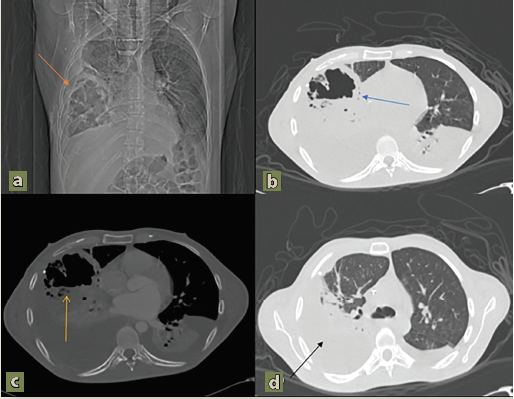

Se le dio el alta con valproato de magnesio; 15 meses después del inicio de la sintomatología neurológica fue ingresado por presentar alzas térmicas, dificultad respiratoria y tos productiva, por lo cual fue ingresado al nosocomio cumpliendo criterios de neumonía adquirida en la comunidad, la cual fue tratada con un triple esquema antibiótico, sin mejoría. En el hospital se le realizó una tomografía, la cual fue compatible con hemotórax y un absceso pulmonar tabicado, por lo que se dio manejo antibiótico y se drenó. Durante su estancia, el paciente perdió aproximadamente 5 kilos y presentó incapacidad para alimentarse, por lo que se utilizó nutrición parenteral ante la dificultad de llevar a cabo el procedimiento quirúrgico por la enfermedad priónica. El paciente permaneció 25 días hospitalizado hasta fallecer de sepsis con origen pulmonar. No fue realizada necropsia por falta de condiciones de seguridad adecuadas por parte del servicio de patología.

Durante su ingreso recibió tratamiento para el absceso pulmonar (figura 2) a base de meropenem, el cual fue secundario a la neumonía que presento, esto atribuible a su condición neurológica, así mismo recibieron manejo las complicaciones asociadas como desequilibrio hidroelectrolítico, permaneciendo en el nosocomio 17 días hasta su fallecimiento.

Imágenes: Guevara et al.

Figura 2 a, b, c) La arquitectura del parénquima pulmonar se encuentra alterada a expensas de imagen que se localiza el lóbulo medio e inferior del pulmón derecho, de características ovoide, paredes engrosadas, irregulares, con interior líquido-aire, que realza de forma difusa tras la administración de medio de contraste, mide aproximadamente 8.3 x 7.7 x 8.2 cm en sus ejes mayores para un volumen aproximado de 274.0 cc, por imagen compatible con parénquima destruido por absceso y presencia de una atelectasia posterobasal izquierda. d) Derrame pleural bilateral de predominio derecho aproximadamente de 50% de este lado con colapso pulmonar pasivo secundario y aspecto lobulado/septado altamente sospechoso de empiema.